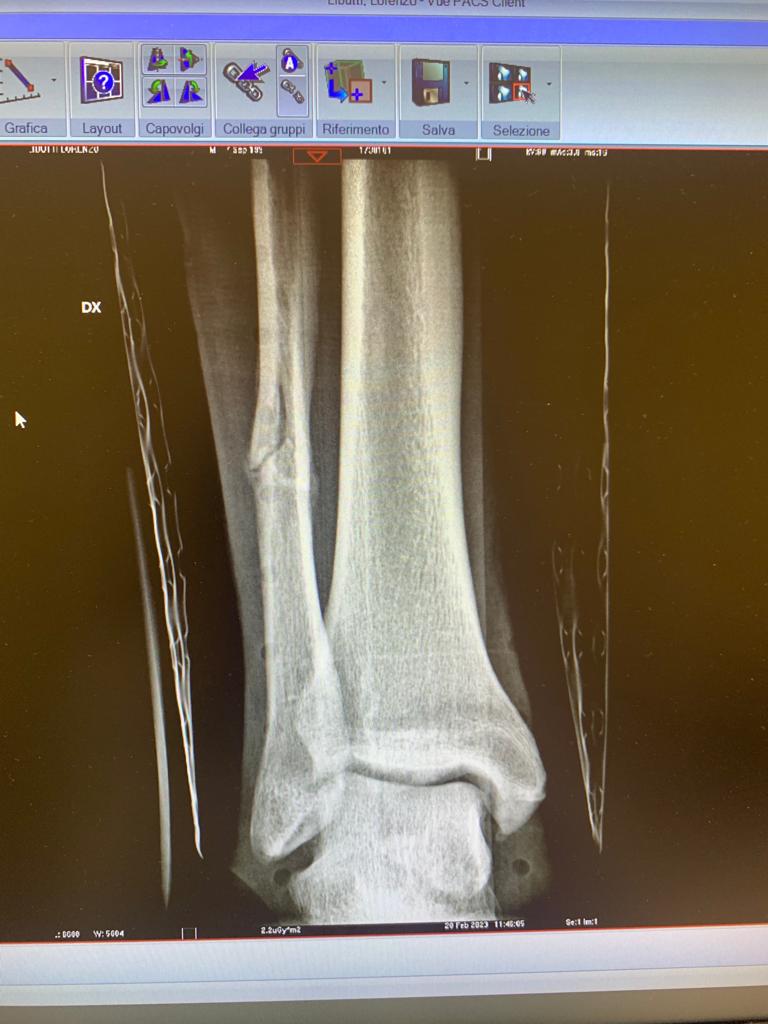

Un infortunio di questo tipo ultimamente è capitato al laterale destro in forza alla Reggiana Lorenzo Libutti. Per Lorenzo la doccia fredda era arrivata sul finire di gennaio al termine di un match dei granata, la diagnosi non lasciava spazio a interpretazioni: frattura del perone! Di seguito potete anche vedere la lastra fatta in ospedale: